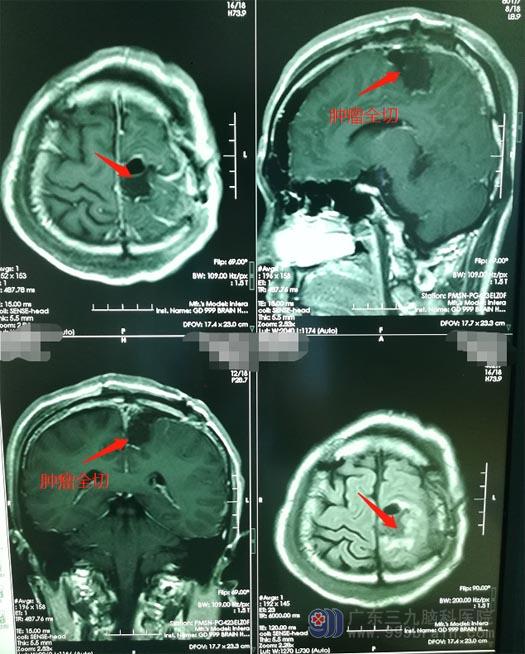

术后第三天,影像复查结果显示:肿瘤已经全切。冯先生肢体活动、语言等都没有任何影响,不久就可以康复出院了。

▲手术后